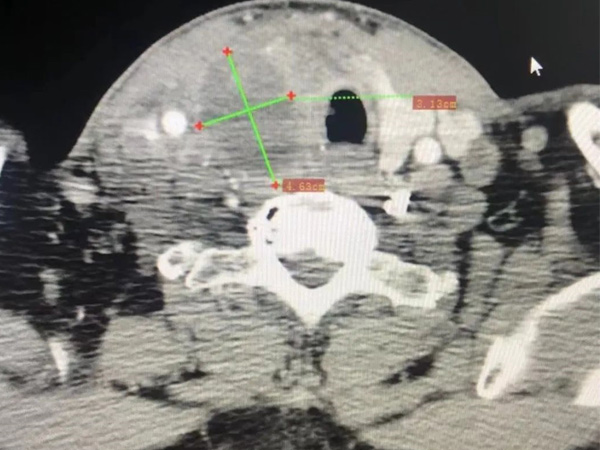

昨日,我院肿瘤科张旭阳主任在局麻下完成云南省第二例氩氦刀冷冻消融术,也是首例甲状腺肉瘤冷冻消融术。

患者肿瘤巨大、坚硬,严重压迫气管,造成频繁的呼吸困难,声音嘶哑,颈部淋巴结转移,剧烈的疼痛,牵扯到头部,影响睡眠。

此前进行一次动脉灌注化疗栓塞术治疗,联合放疗,疼痛症状已经明显缓解,肉眼可见的肿瘤已经明显缩小,但由于肉瘤的坚硬,而且恶性程度是高于癌症的,因此还有呼吸压迫和声音嘶哑症状。在进行有效的气管、皮肤注射隔绝液体保护后,氩氦刀避开众多的颈部大血管、神经、气管,达到病位,在零下170℃低温冷冻下,彻底冻死肿瘤。仅是局麻手术,患者几乎没有痛苦的顺利完成手术。术后,说话声音就比之前清晰,呼吸也比之前畅快。患者术后第一天,张主任与湘雅三院陈学东教授查房,患者症状缓解明显,家属激动的感谢丽江瀚康肿瘤医院给他们带来的希望。

氩氦刀冷冻消融术(图),简称氩氦刀,是一种微创治疗方式,是一种纯物理疗法,是目前癌症肿瘤患者治疗较新的一种治疗手段。氩氦刀是CT或超声的引导下,将冷冻穿刺针插入肿瘤病灶,通过对肿瘤分别注入氩气,制造零下140℃~170℃超低温------相当于月球晚上的温度,快速冷冻肿瘤组织,再启动氦气,使病变组织温度从超低温上升至零上20℃~40℃,从而彻底杀死肿瘤。因为具有真空隔热技术,低温手术系统制冷或加热只局限在冷冻针尖端,针杆又有很好的热绝缘,因此不会对穿刺路径上的组织产生损伤,安全性更高。